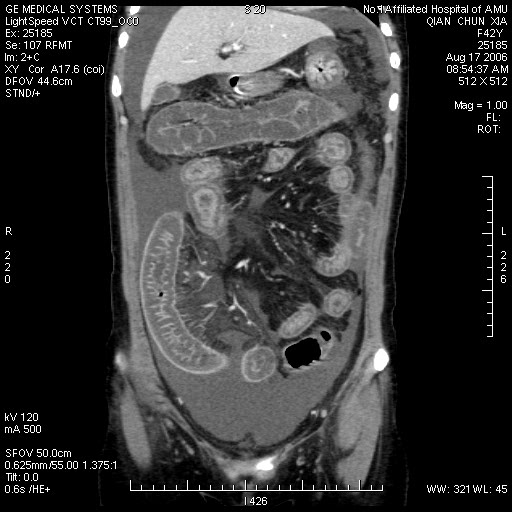

这个病例有脱发的病史,后转到风湿科,确诊为sle,经过一段时间的激素治疗,病情好转,以下是今日复查的ct

系统性红斑狼疮(sle)是一种累及多系统多器官,临床表现复杂,病程迁延反复的自身免疫性疾病。 sle的临床表现无固定模式,病程迁延,反复发作,间有长短不等的缓解期,起病可为暴发性、急性或隐匿性。

其中,消化系统症状:可出现恶心、呕吐、腹痛、腹膜炎、肠系膜血管炎、肝酶增高等。

糖皮质激素治疗,能抑制炎症细胞聚集,具有抗增殖和免疫抑制作用,是最强力的抗炎剂,是治疗sle的最主要药物,是sle的基本疗法。